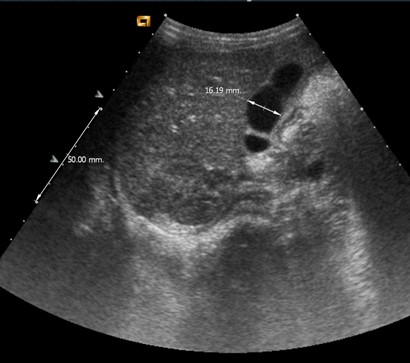

¿Realizaría usted algún estudio complementario tras el alta?